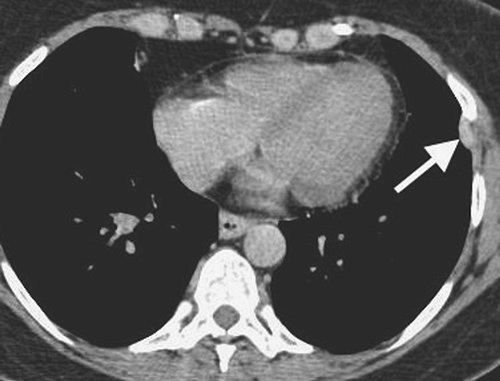

FIGURE 9-10. Hemothorax. CT shows high-attenuation blood (H) in the right pleural space.